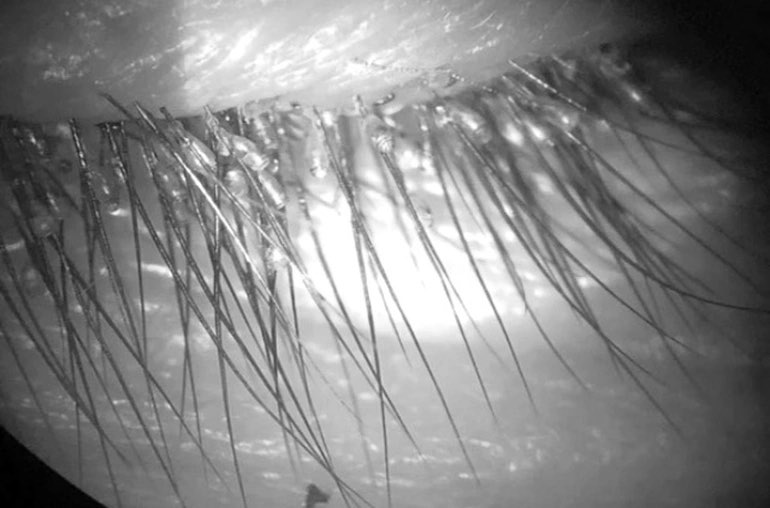

Old  Default Kinh hãi gần 100 con rận mu làm tổ trên mi mắt người đàn ông ở Hà Giang

Bệnh nhân đến viện khám với lý do ngứa mắt nhiều, đã khám và nhỏ thuốc tại một số bệnh viện gần nhà nhưng không khỏi.

Bệnh viện Đa khoa Hùng Vương, Phú Thọ cho biết, bệnh viện vừa tiếp nhận nam bệnh nhân đến khám vì ngứa mắt.

Trường hợp hiếm gặp này là nam bệnh nhân 55 tuổi có địa chỉ tại Hà Giang.

Bệnh nhân đã khám và nhỏ thuốc tại một số bệnh viện gần nhà nhưng không khỏi.

Bác sĩ đã lấy ra gần 100 con rận mu trên mi mắt bệnh nhân.

Đến khám chuyên khoa Mắt tại Bệnh viện đa khoa Hùng Vương, bệnh nhân được kiểm tra mắt bệnh nhân dưới kính sinh hiển vi thì "tá hỏa" vì có hàng trăm ký sinh trùng và trứng ký sinh trên mi mắt bệnh nhân.

Bác sỹ đã gây tê tại chỗ và lấy ra gần 100 ký sinh trùng rận mu và hơn 100 trứng ký sinh.

Bệnh nhân chia sẻ: Gia đình có nuôi gia cầm và gia súc phía dưới sàn nhà và có thể đó là nguyên nhân khiến ông bị nhiễm ký sinh trùng rận mu trên mắt.

Bác sỹ khuyến cáo tới người dân, nên vệ sinh sạch sẽ cơ thể và nhà ở vì ký sinh trùng có thể sinh sống và trú ngụ ở mọi nơi, có thể sống ký sinh trên cơ thể con người.